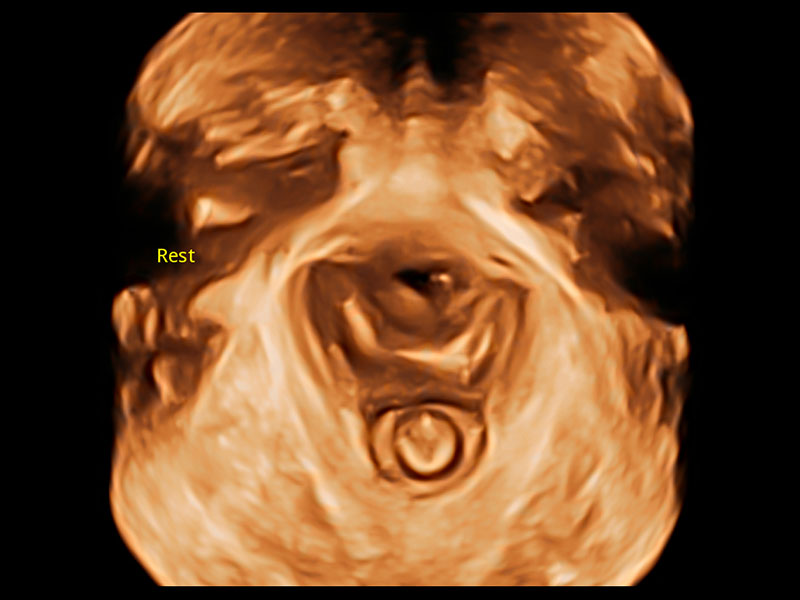

S-Pelvic

S-Pelvic*

S-Pelvic ist ein fortschrittliches Werkzeug, das darauf ausgelegt ist, die Art und Weise zu revolutionieren, wie Kliniker die Beckenbodenfunktionsstörung (PFD) bewerten. Aufgrund seiner hochintelligenten Fähigkeiten ist die vollständige Automatisierung der Erkennung, Nachverfolgung und Messung der Beckenbodenanatomie mit einem einzigen Klick in beispiellosem Komfort möglich. Darüber hinaus erfüllt S-Pelvic die Auto-Anterior-Kompartimentbewertung in 2D und die Auto-Levator-Hiatus-Bewertung in 3D/4D und berücksichtigt sowohl die Ruhe- als auch die Valsalva-Manöver, um möglichst viele Schritte und Details in der Beckenbodenultraschallabdeckung zu berücksichtigen und ein umfassendes Benutzererlebnis zu bieten.

Lev.Hiat A-r: 16.33 cm2

Lev.Hiat H-r: 53.70 mm

Lev.Hiat W-r: 43.96 mm

Lt-LUG-r: 24.16 mm

Rt-LUG-r: 19.94 mm